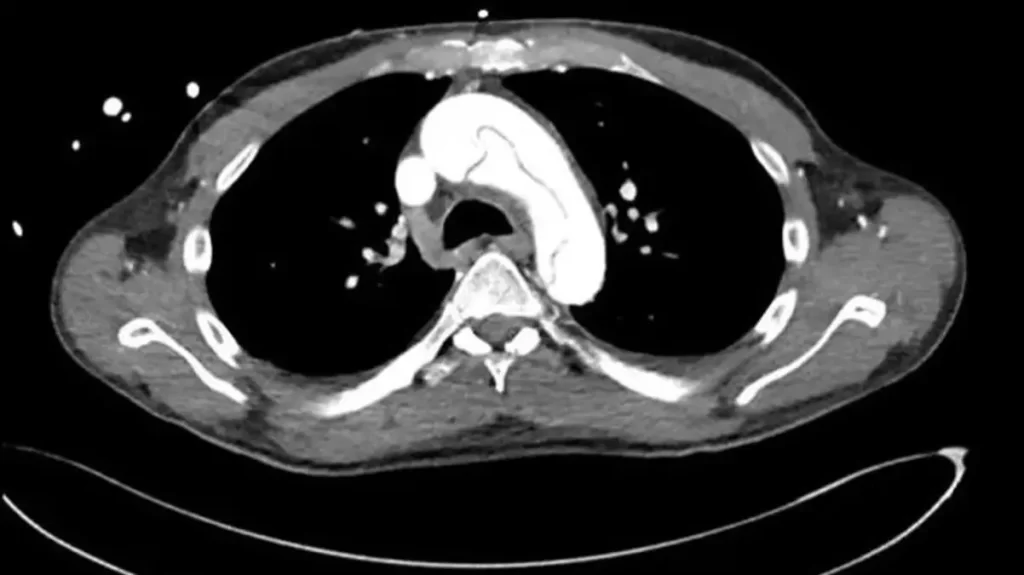

Hastaneye geldiğinde, aşırı düşük kan basıncı ve yavaş nabız tespit edildi. Ultrason taraması, aortun üst kısmında bir yırtık olduğunu gösterdi. Bu durum, acil açık kalp ameliyatı gerektiren hayati bir tehlike oluşturuyordu.

Adam, aort grefti değişimi ameliyatı geçirdi ve iyileştiği bildirildi. Ancak doktorlar, mastürbasyon ile aort yırtılması arasındaki bağlantının tam olarak anlaşılamadığını belirttiler. Kronik pankreatitin önemli bir risk faktörü olabileceğini düşünüyorlar.